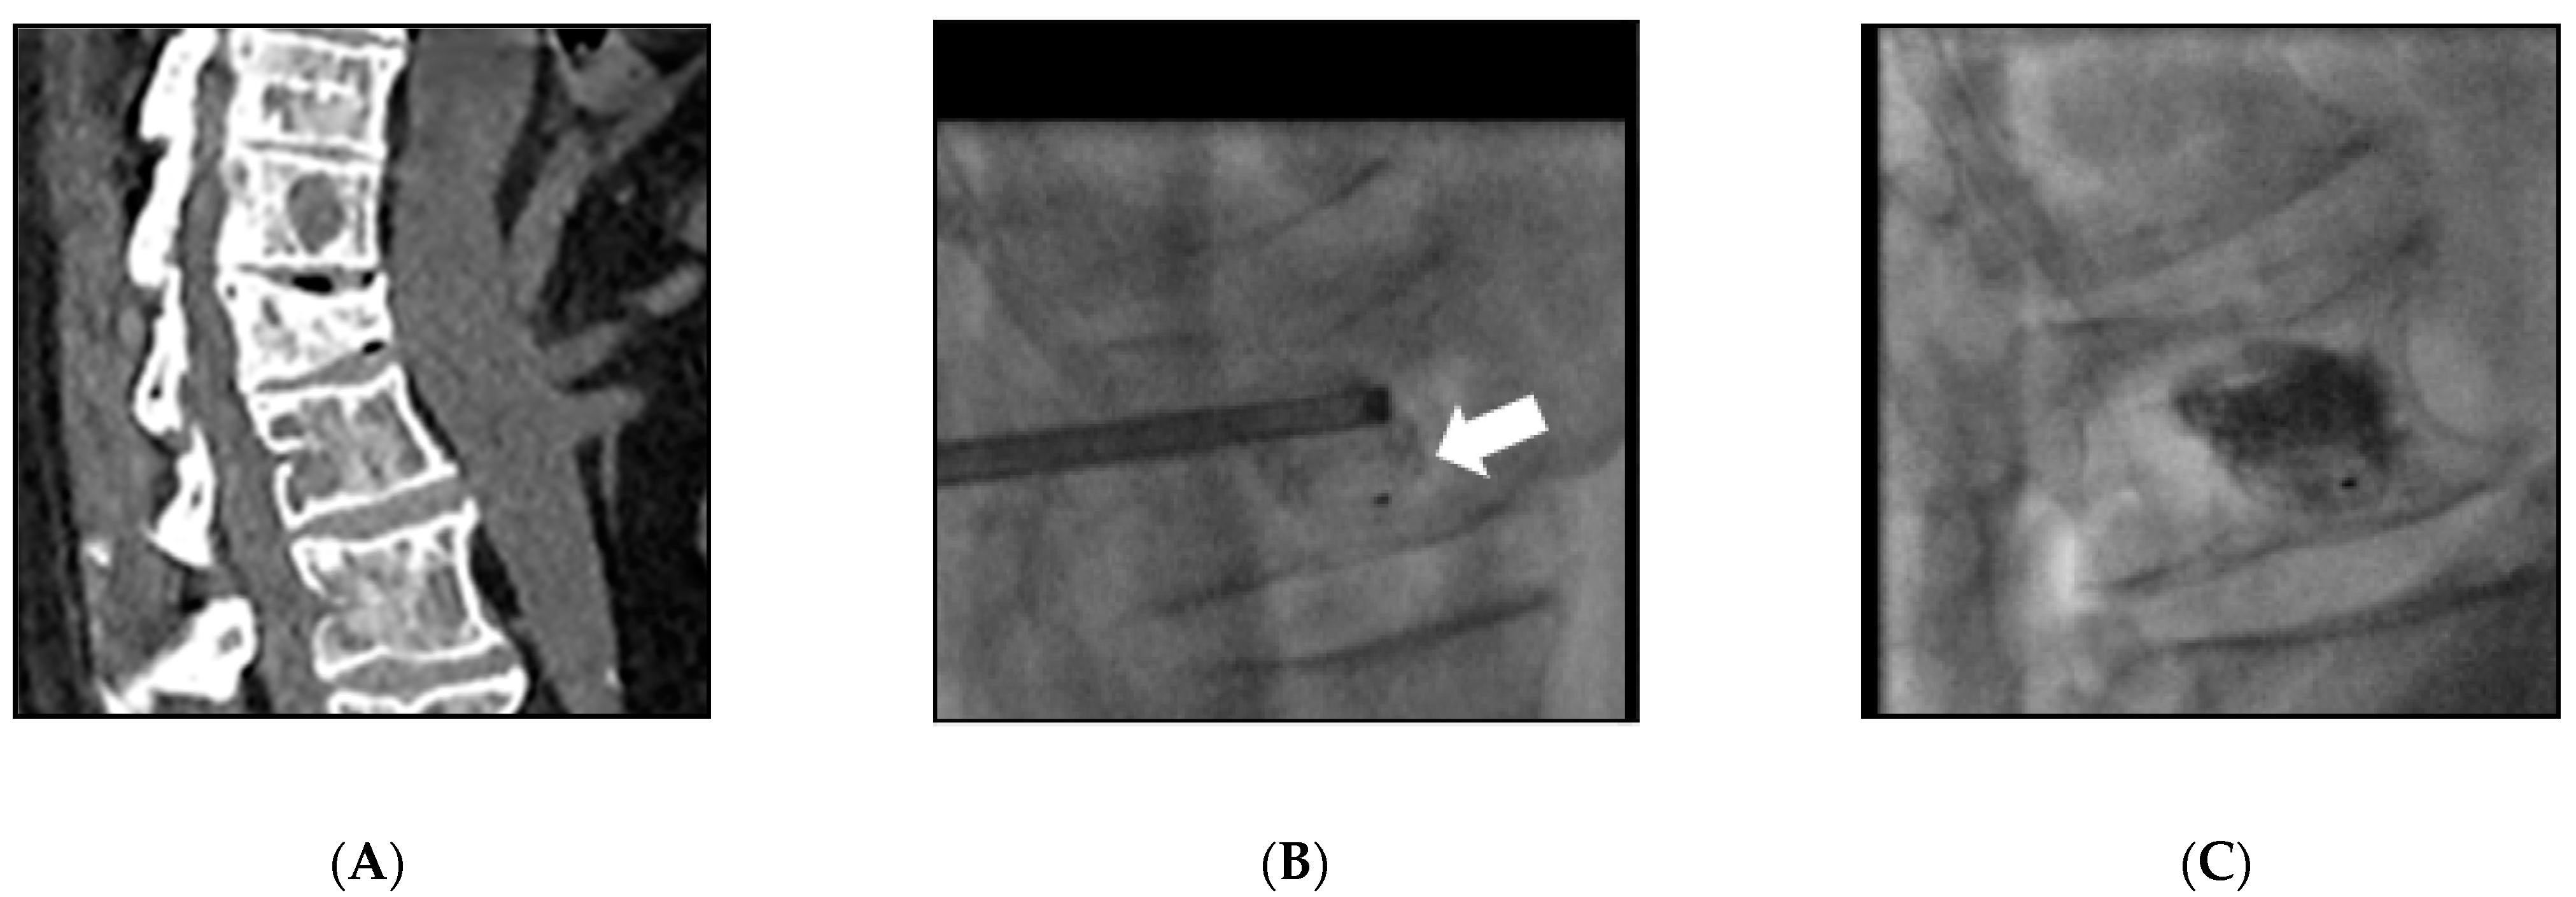

| 1 | 59 | Female | Breast | L2 | 10 | V-strut® (2) | Electrochemotherapy | L2 | Cement leakage (1) | - |

| 2 | 53 | Female | Breast | L4 | 8 | V-strut® (2) | - | - | - | - |

| 3 | 64 | Male | Lung | L2 | 9 | V-strut® (2) | Vertebroplasty | L3 | VCF L4&L5 (2) Cement leakage (1) | Vertebroplasty |

| 4 | 58 | Male | Lung | L4 | 9 | V-strut® (2) | - | - | Cement leakage (1) | - |

| 5 | 54 | Female | Breast | L4 | 10 | V-strut® (2) | Vertebroplasty | L3 | VCF L5 (2) Cement leakage (1) | - |

| 6 | 48 | Male | Lung | L1&L4 | 9 | SpineJack® (4) | Vertebroplasty | T9 T10 T11 T12 | - | - |

| 7 | 62 | Male | Lung | L3 | 9 | SpineJack® (2) | Vertebroplasty | T2 T3 T4 | - | - |

| 8 | 40 | Female | Breast | T8 | 7 | SpineJack® (2) | - | - | - | - |

| 9 | 73 | Female | Breast | L1 | 10 | SpineJack® (2) | - | - | VCF L2 (3) Cement leakage (1) | Spinejack® (2) |

| 10 | 56 | Female | Ovarian | T12 | 12 | SpineJack® (2) | Vertebroplasty | T10 T11 L1 | - | - |

| 11 | 79 | Female | Lung | L1&L2 | 01 | SpineJack® (4) | - | - | - | - |

| 12 | 23 | Female | Osteosarcoma | T12&L1 | 9 | SpineJack® (2) | Vertebroplasty | C7 T3 T5 | Cement leakage (1) | - |

| 13 | 89 | Female | Ovarian | T11&L1 | 10 | SpineJack® (2) | Vertebroplasty | T12 | - | - |

| 14 | 74 | Female | Ovarian | T12&L1 | 10 | SpineJack® (4) | Vertebroplasty | L2 | Cement leakage (1) | - |

| 15 | 59 | Female | Breast | T9 | 9 | Kiva® (1) | - | - | - | - |

| 16 | 57 | Male | Myeloma | L2 | 7 | Kiva® (1) | - | - | - | - |

| 17 | 78 | Male | Lung | T12 | 7 | SpineJack® (2) | Vertebroplasty | T3 T4 | - | - |

| 18 | 49 | Female | Breast | T10 | 7 | Spinejack® (2) | - | - | - | - |